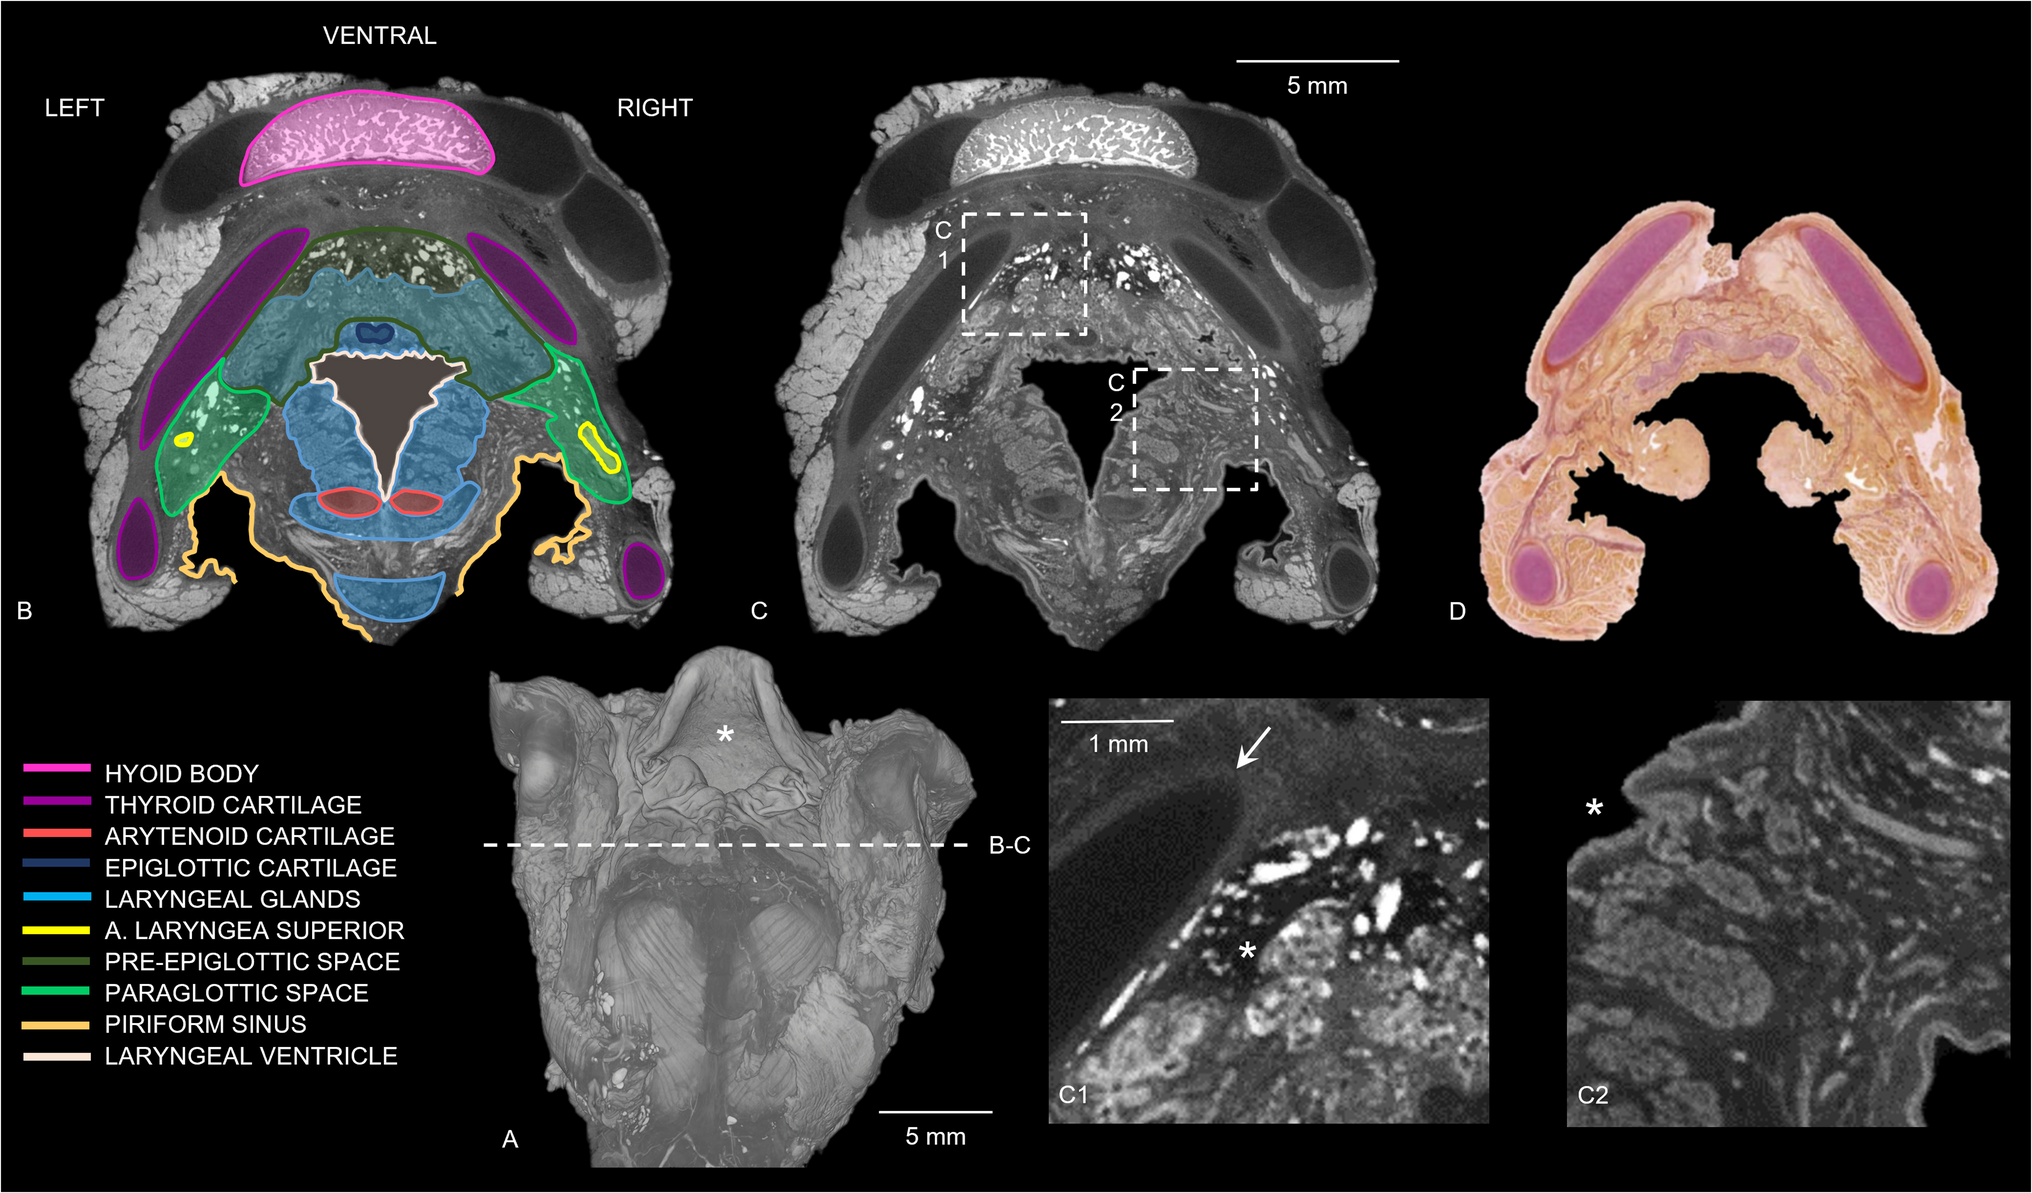

DiceCT revealed uni- or bilateral hyperdense bundles crossing through the thyroid lamina in samples 3 and 5 (Fig. 4). A hyperdense ossification center was identified within the thyroid cartilage in the oldest pediatric sample and in addition some hypodense aspects were found in the cricoid cartilage (Fig. 4). In all specimens, a line with higher density was noted encircling the hypodense cartilage parts of the hyoid (if not completely ossified) and larynx on diceCT (Figs. 4 and 5). Figure 5 shows a 3D diceCT volume rendering and anatomically marked transverse sections of sample 1 to show the detailed visualization of the pediatric hyoid-larynx complex’s anatomy.

Fig. 5

3D diceCT volume rendering and diceCT transverse sections of the sample of the 12-day-old female (case 1) (voxel size 12 μm), anatomically marked and compared with a histological section. (a) 3D diceCT volume rendering, dorsal view, showing the epiglottis (asterisk) and section of (b)-(c). (b) DiceCT transverse slice with anatomically marked sections and locations. (c) Same transverse slice as (a); showing a hyperdense ossified hyoid body, hyperdense connective tissue in paraglottic and pre-epiglottic space and a denser line surrounding the hypodense cartilages. (c1) Section of image (c) showing the denser line around the more hypodense thyroid cartilage (arrow) and hyperdense connective tissue (asterisk) in the pre-epiglottic space. (c2) Section of image c showing individually visible hypodense glands surrounding the laryngeal ventricle (asterisk). (d) Transverse section of the human newborn larynx at 5 mm above the glottis with Elastica van Gieson stain, from “Functional Histoanatomy of the Human Larynx” [19] for comparison of the detailed diceCT image in (c). Note that the hyoid bone is not visualized in the histological section. Adapted with permission from Springer Nature Customer Service Centre GmbH: Springer Singapore, Functional Histoanatomy of the Human Larynx by Kiminori Sato.

Copyright Springer Nature Singapore Pte Ltd. 2018

In addition, a denser layer was observed around the hypodense cartilages in all pediatric samples (Fig. 4). This layer appeared as a hypodense line surrounding the even more hypodense laryngeal cartilages, and in the younger samples, it also encircled the hypodense cartilaginous greater horns of the hyoid (Fig. 5). This could shed light on the cartilage and bone development, as it was not observed in adults [14]. The dense layer could present the outer layer of hyaline cartilage, the perichondrium. With age, the cartilage is subject to the process of endochondral ossification, resulting in the perichondrium being converted into periosteum [20]. Periosteum is a thin layer of membranous connective tissue, while perichondrium is denser and consists of fibrous tissue [22]. Besides, the perichondrium appears thinner on histological slices of the cartilaginous adult larynx in comparison with the pediatric larynx; therefore, it could show less dense on diceCT as well [19].

In two samples, a uni- or bilateral circular defect in the lamina of the thyroid cartilage was observed on micro-CT (Fig. 4). In the literature, this opening is known as the foramen thyroideum (FT) [23]. The FT can occur in one or both laminae of the thyroid cartilage. We found a FT in two of the hyoid-larynx complexes (40%), in one sample unilateral and in the other one bilateral. Previous research reports an incidence of FT in adults of 24–31%, of which 2–11% were found bilaterally [2325]. The prevalences found in this study showed a slight difference in comparison to current literature, which could be due to our small sample size. According to León et al. [25], the adult FT contains a neurovascular bundle in 73%, a nerve branch in 20%, and in 7% only a vascular branch. In our research, diceCT showed a hyperdense bundle within every FT. Within those hyperdense bundles, two hypodense tubular structures could be visualized in one sample, and the other sample showed one hypodense and one hyperdense tubular structure (Fig. 4). Since blood shows hyperdense on diceCT images, we suspect that the hypodense tubular structures are nerves (branch of the superior laryngeal nerve) and the hyperdense structures are blood-filled vascular branches. As neurovascular bundles are surrounded by connective tissue, the hyperdense staining surrounding the bundles is considered connective tissue. This is in line with the hyperdensely stained tissue we discovered in the cricoid area, paraglottic, and pre-epiglottic spaces (Fig. 5). These spaces contain areolar or loose connective tissue, which is composed of adipose tissue with elastic and collagen fibers [22]. Hence, B-Lugol binds to adipose tissue and/or elastic and collagen fibers as well. Anatomical dissection could provide a definitive answer to the content of the FT.